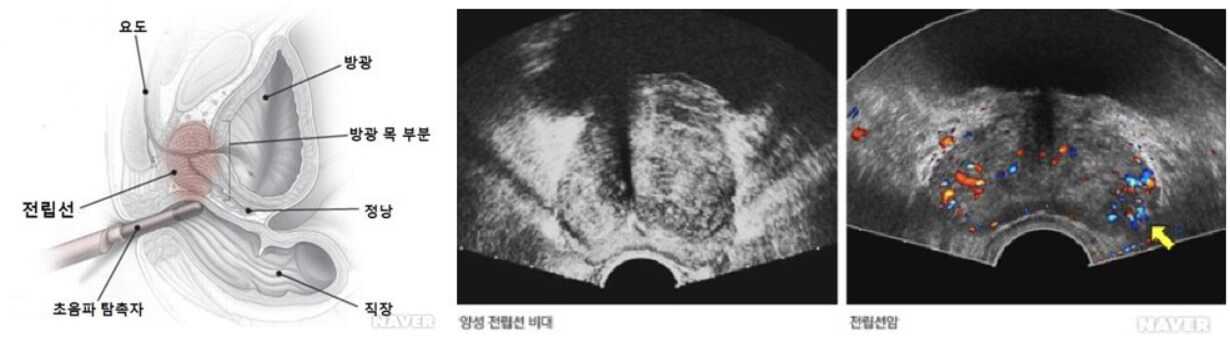

경직장 전립선 초음파는 항문을 통하여 직장 내 초음파 탐촉자를 삽입하여 직장의 전방에 위치하는 전립선의 이상을 진단하는 검사법이다. 전립선을 검사하는 데에는 경복부 초음파(transabdominal ultrasound)도 가능하지만 전립선의 크기가 작고 좁은 골반강의 최하부에 있기 때문에 좋은 음창(sonic window)을 얻기 어려울 수 있다. 전립선은 하부 직장의 전방에 인접하고 있어 경직장 초음파를 이용하면 적절한 음창을 얻을 뿐만 아니라 해부학적인 구조물 주변구역(peripheral zone), 중심구역(central zone)을 상세히 볼 수 있다. 가장 정확한 전립선의 구조물을 볼 수 있는 영상 검사로는 전립선 자기공명영상(MRI)이 있으나 비용 측면에서 모든 환자에게 적용하기는 어렵다.경직장 전립선 초음파의 경우 흔한 양성 전립선 비대증 진단, 전립선의 크기와 부피를 측정하는 데 유용하다. 일반적으로 혈장 전립선 특이항원(prostat- specific antigen, PSA)의 증가와 직장수지 검사(digital rectal examination, DRE)에서 만져지는 병변이 있을 때는 초음파 유도 하 전립선 생검(sextant biopsy)을 시행하며, 이 방법이 진단에 가장 정확하다.

환자는 좌측 와위(왼쪽으로 돌아 누운 자세)를 취하고 젤을 바른 막대형 탐촉자를 약 10cm 전후로 전립선이 보일 만큼 항문을 통해 직장에 삽입하고 검사가 진행된다.

전립선 암, 전립선 비대증